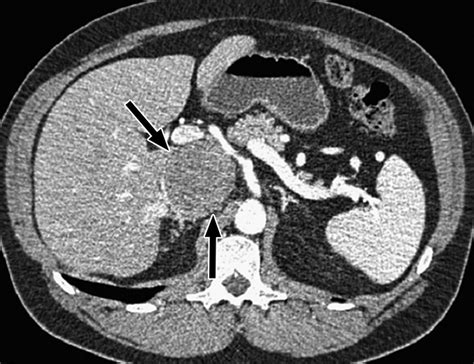

• CT Scan: A computed tomography (CT) scan provides detailed images of the veins and can help identify the cause of dilation.